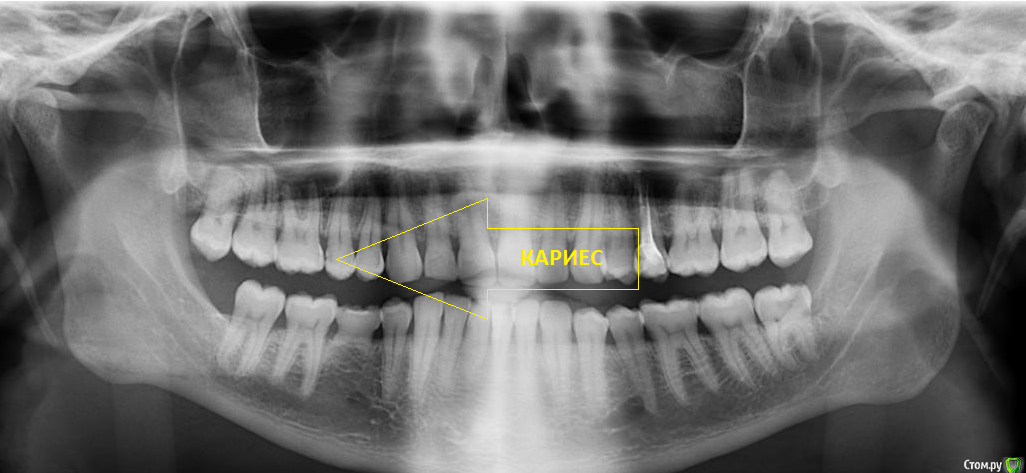

Romko Опубликовано 5 мая, 2016 Поделиться Опубликовано 5 мая, 2016 Недавно откололась часть зуба, пришлось идти в стоматологию. Зуб залечили. Заодно решил сделать снимок, основная цель была посмотреть - что там с молочным зубом и ждать ли коренной. Врач сказала - зародыша коренного нет и его ждать бесполезно(да?). И корни почти растворились, скоро ему "ой всё". Собственно, волнуют вопросы: Коренного действительно не ждать? Сколько, примерно, может еще "прожить" молочный? И куда мог деться зародыш коренного и зуб мудрости с той же стороны. Я его не удалял(вообще не удалял ни одного коренного зуба еще). Но нет ни самого зуба мудрости, ни зародыша. Ссылка на комментарий

Romko Опубликовано 6 мая, 2016 Автор Поделиться Опубликовано 6 мая, 2016 (изменено) @___49___, да, спасибо. Несколько "кариесов" и удаление зубов мудрости(вроде, сказали, все 3 удалять) на очереди, отложено на "послемайские"... К удалению еще морально подготовиться надо, страшно... Это был вообще мой первый визит к стоматологу не считая лечения/удаления молочных зубов в детстве еще во времена советской медицины. Изменено 6 мая, 2016 пользователем Romko Ссылка на комментарий